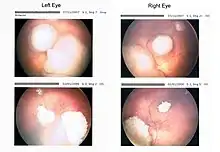

Drawing of a large retinoblastoma

Aspect of trilateral retinoblastoma on MRI

An ocular ultrasound of a large retinoblastoma tumor within the eye of a 3-year-old boy

Funduscopic finding of a retinoblastoma

Ocular fundus aspect of retinoblastoma

Large exophytic white tumor with foci of calcification producing total exudative retinal detachment